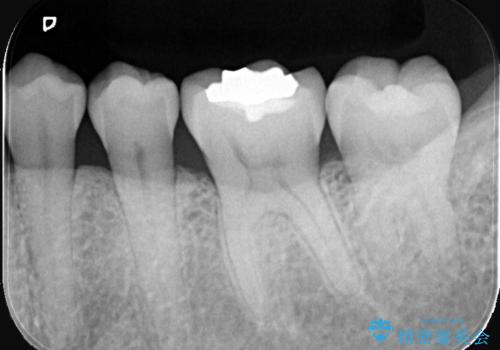

歯が欠けたことによるものか、もしくは以前装着された修復物の不適合が原因と考えられますが、銀歯(メタルインレー)と歯との間に大きな段差が認められ、汚れが溜まりやすい状態となっていました。

このような状態では、修復物の内部で虫歯が進行している可能性が高いため、治療が必要と判断しました。

今回は、経年的な劣化が少なく、汚れが付着しにくいセラミックインレーを用いて治療を行いました。